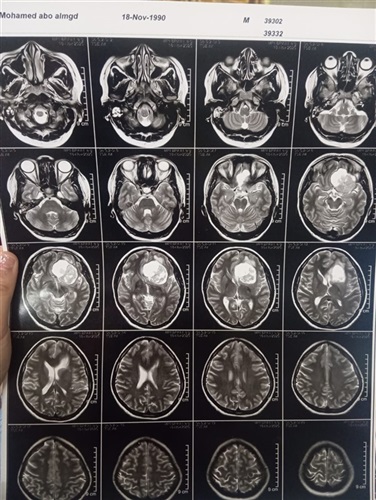

ومن جانبه، أوضح الدكتور مجدي القاضي عميد كلية الطب البشري ورئيس مجلس إدارة المستشفيات الجامعية أن المريضة حضرت وهي تعاني من صداع شديد وارتفاع بضغط المخ مع تدهور ملحوظ في حدة الإبصار، وبإجراء الفحوصات الطبية اللازمة وأشعة الرنين المغناطيسي، تبيّن وجود ورم كبير بقاع الجمجمة ضاغط على أعصاب البصر والأوعية الدموية المغذية للمخ، ما استدعى التدخل الجراحي العاجل باستخدام أحدث التقنيات الدقيقة.